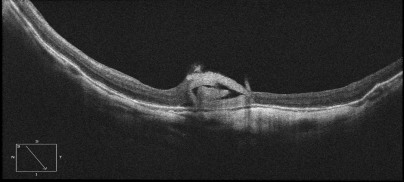

患者于某,女,52岁,因左眼视力下降一年入院,入院时左眼视力为数值/30cm,诊断为左眼黄斑裂孔,在我科行左眼玻璃体切割联合生物羊膜填塞黄斑裂孔,术后一周复查OCT可见黄斑裂孔已基本修复,如下图所示: